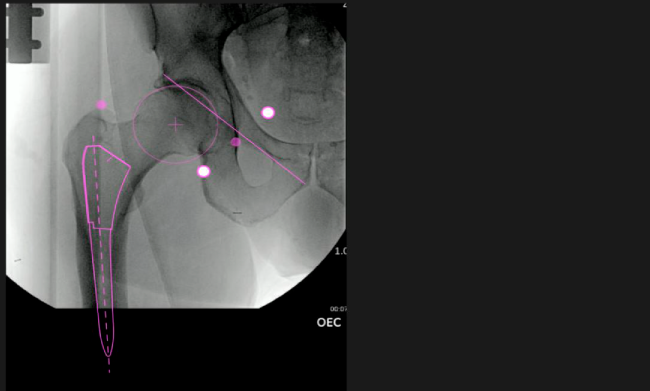

Mayor nivel de información intraoperatoria facilita la colocación correcta de los implantes:

• Inclinación y anteversión de la copa acetabular para una correcta colocación del implante.

• Desplazamiento y offset para posicionamiento óptimo del componente (vástago) femoral.

• Verificación de la posición deseada del implante que potencialmente puede ayudar a reducir la probabilidad de dislocación protésica y aumentar la estabilidad de la articulación.

• Anotaciones digitales y herramientas de análisis de longitud de pierna.

• Con tecnología ONETRIAL® que calcula automáticamente el cambio en la longitud de la pierna y el desplazamiento para todas las combinaciones de implantes en una tabla fácil de leer.